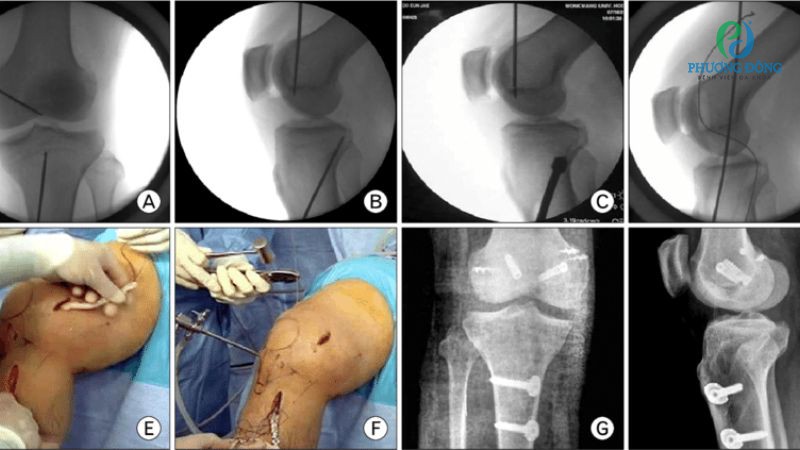

Hình ảnh phương pháp mổ nội soi tái tạo dây chằng chéo trước

- Bước 4: Bác sĩ rạch một đường tiêu chuẩn trên xương chày, nằm giữa củ chày và đường viền giữa xương chày để đưa thiết bị chuyên dụng vào bên trong khớp.

- Bước 5: Tiến hành quan sát tổn thương dây chằng chéo trước, can thiệp thông qua hình ảnh được phóng đại trên màn hình lớn.

- Bước 6: Đóng vết mổ sau khi hoàn thành các sữa chữa tổn thương, cố định bằng nẹp Orbe.